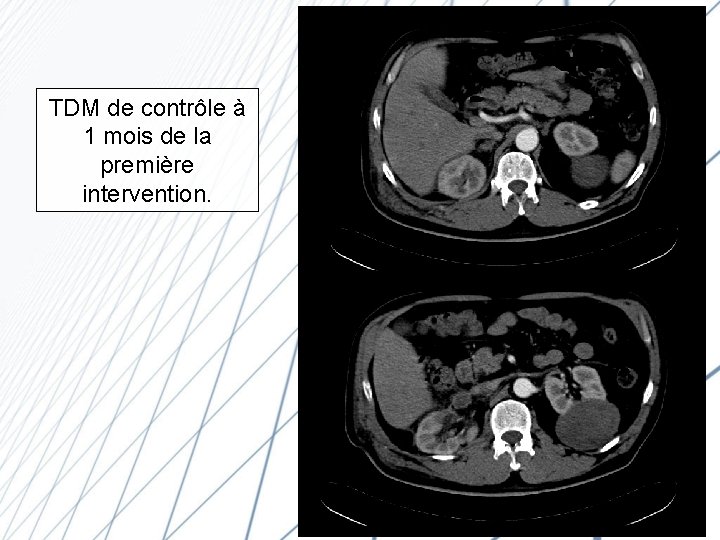

TDM de contrôle à 1 mois de la première intervention.